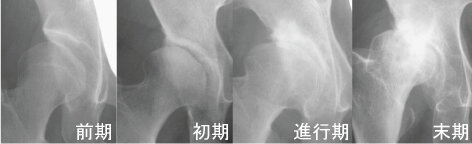

関節の軟骨が摩り減ることで起こる病気で、人工股関節の手術を受ける大半の患者さんがこの病気です。臼蓋形成不全(股関節の骨盤側の受け皿の部分が浅い)や先天性股関節脱臼(赤ちゃんの時に股関節が脱臼する)のある方は軟骨が摩り減りやすく、中年以降に痛みが出て、早い人では50歳ぐらいで軟骨が完全にすり切れてしまい手術が必要な状態になることもあります。痛みが軽いうちはお薬や運動療法(体操)などの保存療法(手術をしない治療)を行いますが、痛みが日常生活やスポーツなどのレクリエーションに支障になると、次は手術療法が必要になります。軟骨の摩り減りが少ない初期の段階であれば自分の骨を利用した手術(骨切り手術)で痛みが取れることがありますが、末期の状態になると痛みやこわばりが強くなり、人工股関節手術が必要になります。先天的な形の変化がない人でも70歳をすぎてから急にこの病気にかかる方が最近増えており、そのような方は痛みが強く手術が必要になる場合が多いです。

関節の隙間(軟骨層)が進行に伴い徐々に消失し、骨頭の変形を生じる。